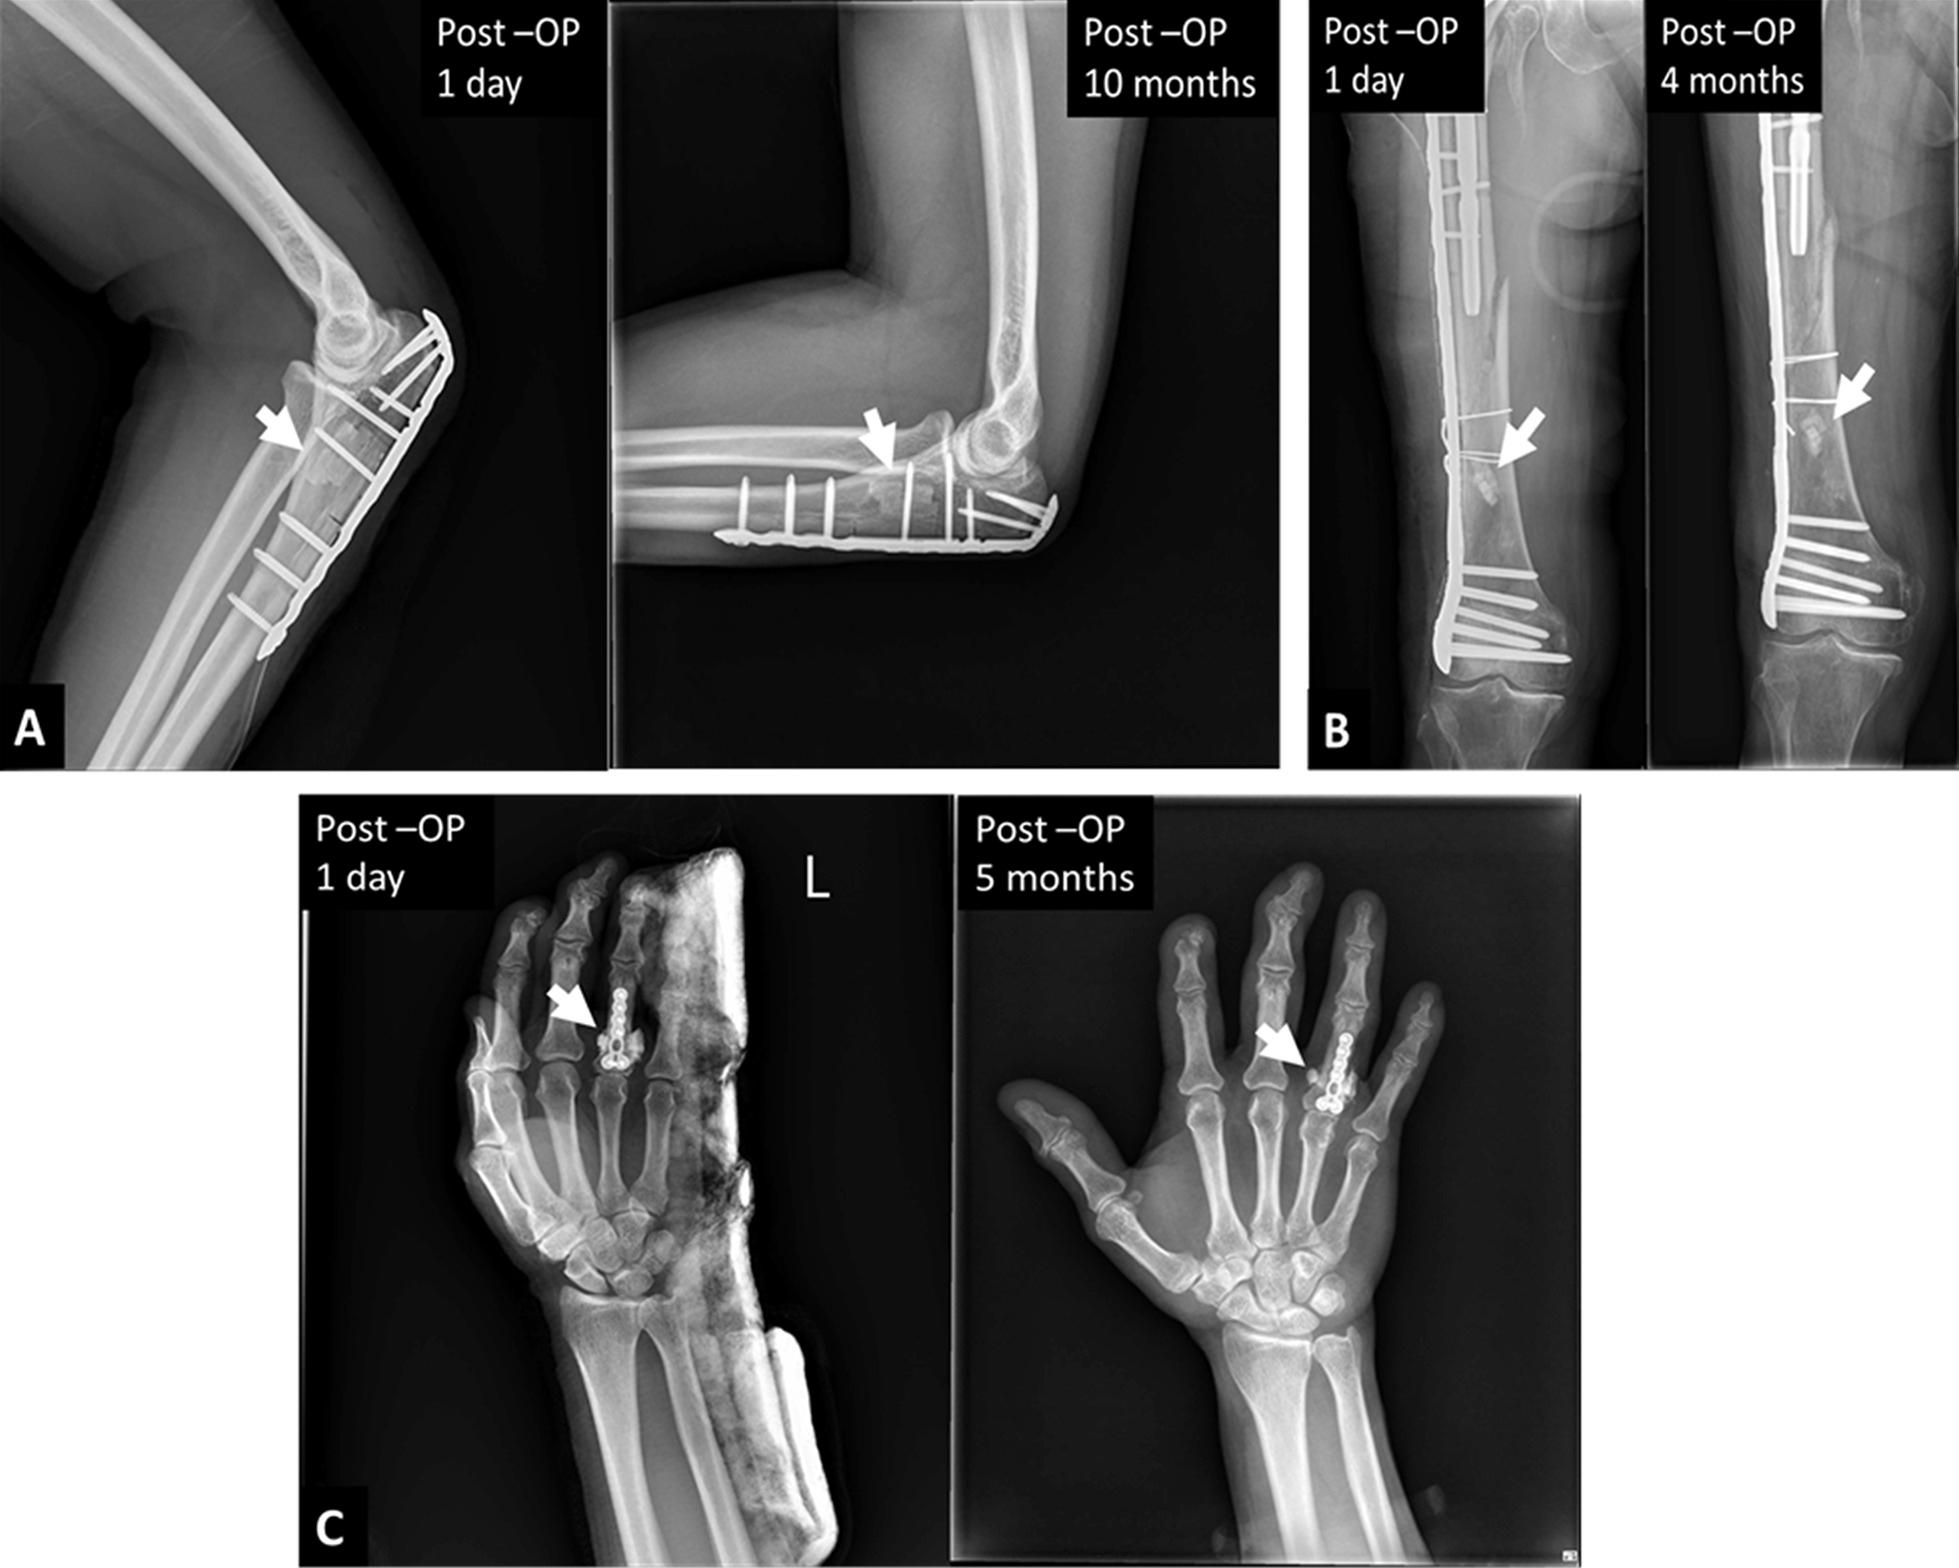

When a fracture goes into or around a joint, it usually damages the cartilage at the ends of bones and other joint tissue. As a result, the affected joints are prone to traumatic arthritis, leading to stiffness. Repairing bone damage, maintaining joint integrity, and avoiding subchondral and metaphyseal defects caused by comminuted fractures is often a great challenge for orthopedic surgeons. Tissue engineering of synthetic bone substitutes has proven beneficial to the attachment and proliferation of bone cells, promoting the formation of mature tissues with sufficient mechanical strength and has become a promising alternative to autograft methods. The purpose of this study is to retrospectively evaluate the clinical outcome and efficacy of a novel synthetic, highly biocompatible, and fully resorbable Ca/P/S-based bone substitute based on medical image findings.

A synthetic, inorganic and highly porous Ca/P/S-based bone-substituting material (Ezechbone® Granule, CBS-400) has been developed by National Cheng-Kung University. We collected fourteen cases of complex intra- and peri-articular fractures with Ezechbone® Granule bone grafting between 2019/11 and 2021/11. We studied the evidence of bone healing by reviewing, interpreting and analyzing the medical image recordings.

RESULTS

In the present study, CBS-400 was observed to quickly integrate into surrounding bone within three weeks after grafting during the initial callus formation of the early stage of repair. All of these cases healed entirely within three months. In addition, the patient may return to daily life function after 3.5 months of follow-up and rehabilitation treatment.

Ezechbone® Granule CBS-400 was proved capable of promoting bone healing and early rehabilitation to prevent soft tissue adhesions and joint contractures. Moreover, it has a high potential for avoiding ectopic bone formation or abnormal synostosis.